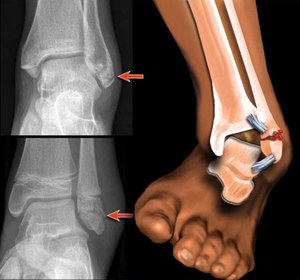

Голеностопный сустав — великий труженик, наша опора, он принимает на себя вес всего тела. Это сочленение сложное, в его составе — три кости (большеберцовая, малоберцовая и таранная). Берцовые кости голени образуют две лодыжки — внутреннюю и наружную, они охватывают таранную кость наподобие вилки.

Вся эта конструкция надежно укреплена связками с внутренней и наружной стороны, есть еще одна связка между берцовыми костями для дополнительной фиксации. Но именно этот сустав больше других и подвержен травмам.

Если же вам не повезло, и связки порвались полностью — формируется полный вывих. В результате смещения костей происходит резкая деформация голеностопного сустава, он распухает, активные движения становятся невозможными, любая попытка это сделать причиняет резкую боль. Полный вывих голеностопа редко бывает без перелома лодыжек — наружной, внутренней или сразу обеих. Через 2-3 часа появляется синева — следствие кровоизлияния в мягкие ткани.

2. Разрыв связок с подвывихом стопы.

3. Перелом лодыжки (или щиколотки, что одно и тоже).

4. Полный вывих в голеностопном суставе.

5. Полный вывих с переломом лодыжек (что встречается наиболее часто).

Полный вывих — это серьезно. И сложно. Вывихи вправляют. Это больно. Лучше это делать под внутривенным обезболиванием или спинномозговой анестезией.